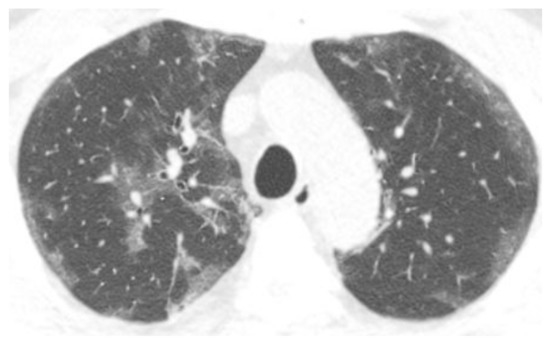

3.3. Chest CT Scans Were Performed in the Subacute Phase (5–12 Days)

3.4. Chest CT Scans Were Performed in the Persistent Phase (13–28 Days)